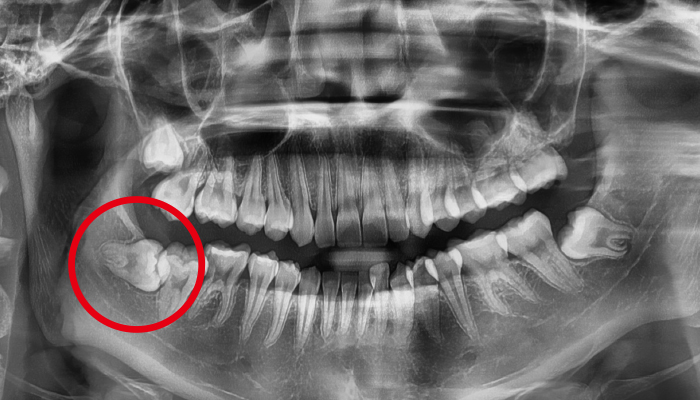

사랑니 발치 전후 사례

• 치료 전

치료 후